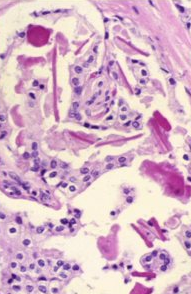

Eosinophilic Amorphous secretions (an intraluminal feature of prostate carcinoma)